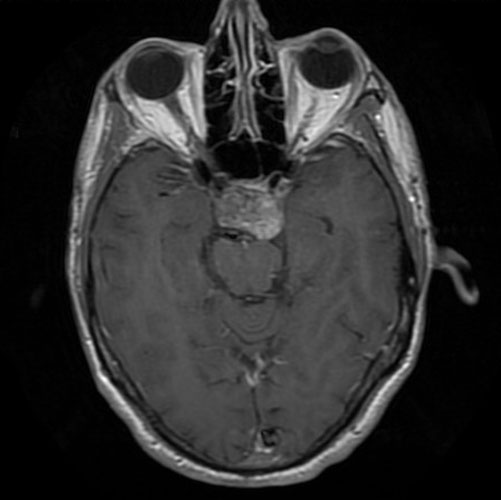

The patient was a 51 year-old man who was referred to this institute for treatment of a sellar mass. MRI revealed a 2.7 x 1.9 cm mass in the sellar region suggestive of a macroadenoma. A transphenoidal resection was performed and yielded the following images.

Pathology of the Case: The MRI images clearly indicate the location of the lesion is in the sellar region with expansion of the sellar. Radiographically, the lesion is well-circumscribed and most consistent with a macroadenoma. The histologic details of the permanent section can be viewed in that online slide (Panel A).